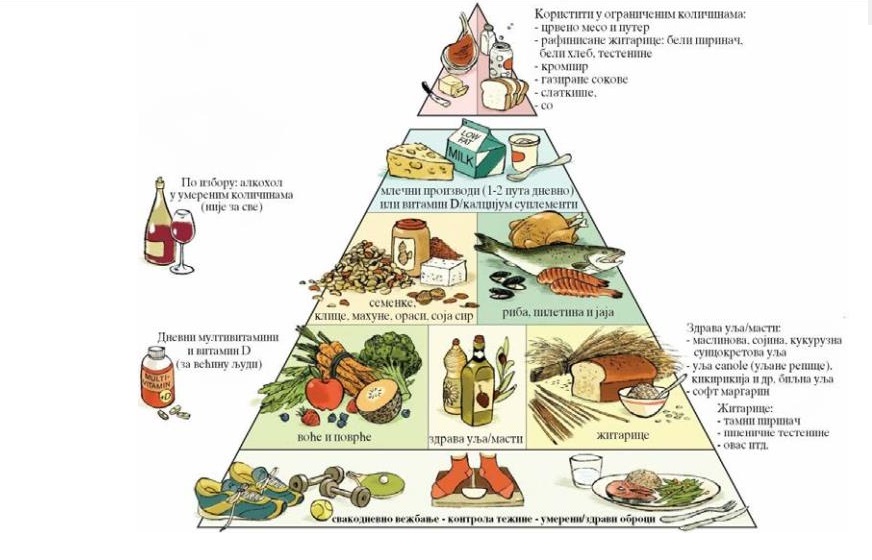

Како би се олакшао и упростио поступак састављања јеловника за дијабетичаре - уведено је рачунање. Рачунање замењује мерење хране вагом. Пошто се 60% потреба добија из угљених хидрата, потребно је упознати угљенохидратну или шећерну јединицу. Треба знати рачунати колико сваки оброк има шећерних јединица, калорија, слатког индекса, итд. |

У условима нормалне исхране не долази до дефицита Ц витамина јер човек из воћа и поврћа задовољава 90 % потреба, млека и млечних производа 5 %, јаја, рибе и меса 1 % потреба. |

| Централно место у лечењу гојазности, хипертензије и резистенције на инсулин код деце представља регулација енергетске равнотеже у склопу промене начина исхране, повећања физичке активности и избегавања претераног седења. Рана идентификација деце са ризиком развоја метаболичког синдрома и даљом прогресијом у дијабетес типа 2 и кардиоваскуларно обољење касније у животу, од великог је значаја за њихову даљу будућност. |